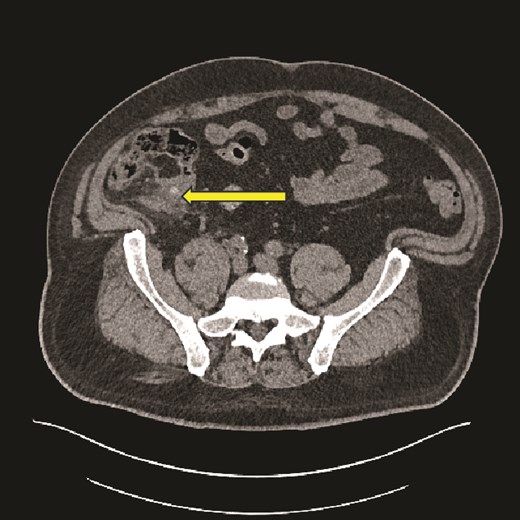

Axial CT image showing caecal inflammation and peri caecal stranding (arrow).

Computed tomography (CT) scan abdomen and pelvis was reported as follows: ‘Inflammatory phlegmon, fat stranding, free fluid, and reactive lymphadenopathy in the right iliac fossa. At the centre of the inflammatory phlegmon there is a dilated appendix with thickened walls. Small appendicolith at the base. Incidental note of a 3.2 cm caecal lipoma, which resides just below the ileocecal valve.’ (Figs 1–3).